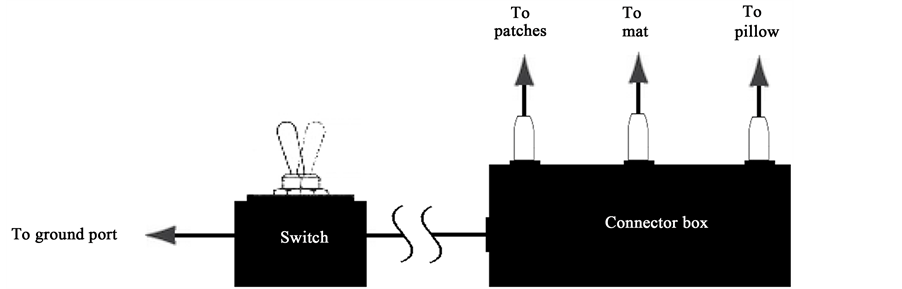

With the continuous color palette used by the software (modified Rainbow Chrome) it has been found that optimal imaging to differentiate between colors is obtained with a 7˚C temperature span (we will be using simply the word “span” to mean “temperature span” for the rest of this paper) between the coolest and warmest temperatures covered by the color palette. Span is defined as the number of degrees selected within a thermal image to best portray highest temperatures compared to the lowest temperatures while using a gray or color palette (Figure 1). Skin temperatures range from 20˚C to 38˚C thus positioning the temperature span above or below that range will render an all white or all back portrayal of that image. This can be seen clearly from Figure 2.

Figure 1. On the left side emphasis is put on the color distribution of the 7˚C span according to the modified Rainbow Chrome color palette. In this case, the span is between 28.13˚C and 35.13˚C. These maximum to minimum temperatures are adjusted to allow best view of color transitions on the areas of interest in the picture to the right (this is called span positioning).

After TI was done, each subject moved to a comfortable recliner chair set up in the same room for the grounding (sham-grounding) session. The reclining angle of the chair was adjusted to a comfortable 30 degrees in respect to the plane of the floor. The chair back and seat were covered with a grounding mat. A grounding pillow was placed at the head position with a Styrofoam pad positioned under the pillow on each side to help stabilize the head and minimize movements. Patches were placed on both palms and soles (total of four patches). The connector ends of the wires from the patches, pillow and mat were inserted into the jacks of a connector box placed next to the recliner. A single wire connected the connector box to a ground port of an adjacent power outlet. A switch was installed on the wire from the connector box to the ground port to permit transference or blockage of the Earth’s electrons (permitting or blocking conduction). This is schematically represented in Figure 3.

Figure 3. Grounding system comprising the connector box, including wires from patches, mat and pillow connected to it, with a wire going to a switch and then to the ground port of a power outlet.